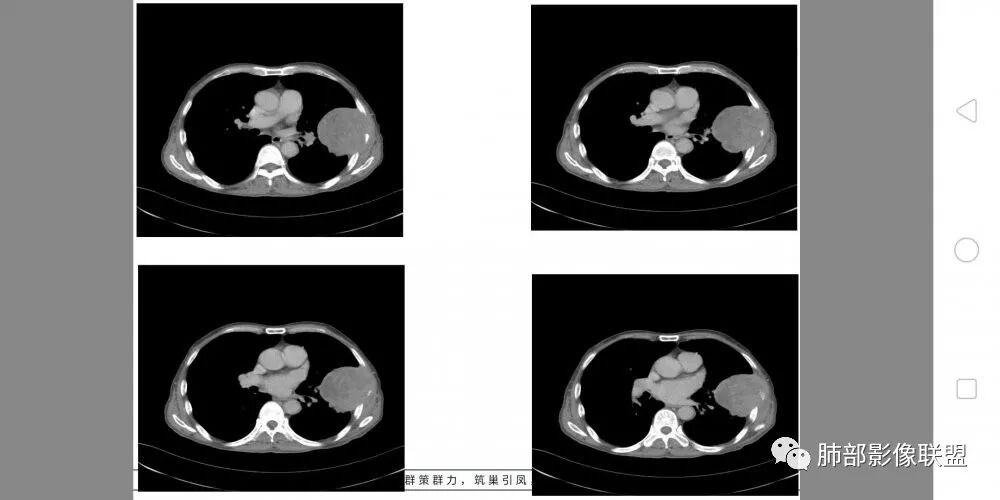

我们根据征象找真相

病灶与叶裂之间夹有上叶下舌段支气管、血管。舌段支气管后移,尖后段支气管前移,病灶将支气管撑开。

叶裂受压后移,提示病灶不来源于叶裂。

内朝外?外朝内?

支气管推移-----提示外朝内

近端肺动脉受压外移,但是有部分进入病灶内-------提示与肺有千丝万缕的关系。

胸壁来源符合吗?

不符合,因为病灶的主体在肺内,而且胸膜在病灶的外侧为主

与胸膜非钝角相交

病灶的整体形态--肺内边界清晰,膨胀性为主

如果是外面长进来的,胸膜掀起的角度一般更大,呈钝角

我们换个角度讲,如果是胸壁肋骨来源,病灶外朝内生长,并且朝内生长这么大,按理说应该是内侧侵袭性强,外侧侵袭弱。但是看这个病灶,外侧边界反而不清,内侧边界清,整个形态不太符合肋骨来源,而且胸膜局部增厚也不太符合胸壁来源。我认为肋骨来源应该以肋骨为中心,偏侧可以,但不会这么明显。而且血供也不一致,应该是肋间或胸壁动脉明显。

肋骨内侧面破坏为主,朝外有轻微的推移迹象。我觉得胸壁来源的放后面,特别是支气管的堵塞,这是肺外病变很少见的,SFT也有,罕见。

胸膜来源侵袭性SFT?肺内恶性肿瘤?

胸膜的孤立的侵袭性SFT一般骨质破坏没有这么厉害。

综合考虑恶性肿瘤,外朝内发展,倾向于肺内来源。